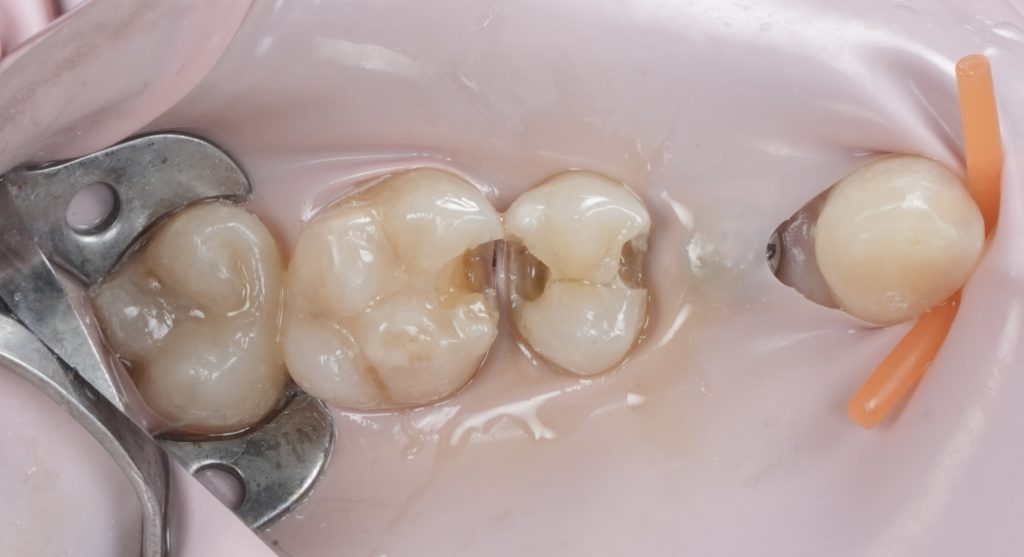

- Fig. 5: Prepared cavity occlusal view.

- Fig. 6: Proximal box close-up (after caries removal).

Images to place

- Fig. 10: Proximal wall formed (band still in place).